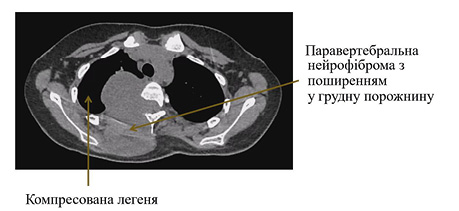

Діагноз: множинні паравертебральні нейрофіброми на рівні Th1-Th7 хребців з поширенням у грудну порожнину та праві відділи хребтового каналу (рис. 7).

Рис. 7. Передопераційний знімок КТ, який демонструє ступінь компресії легені пухлиною